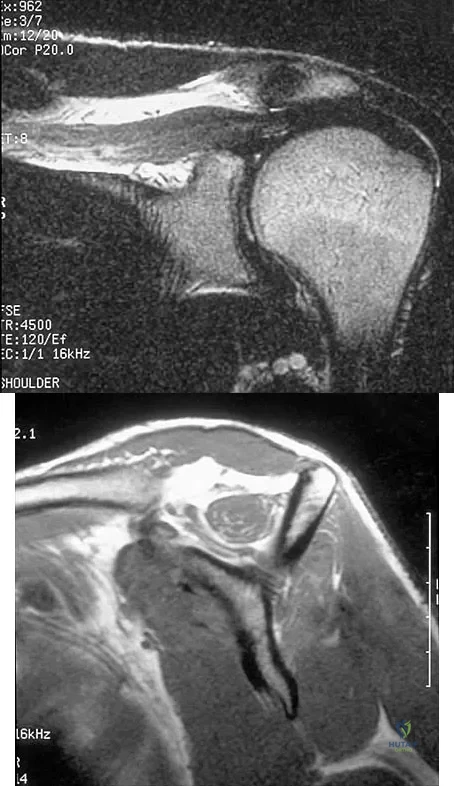

Figures 36a and 36b show the MRI scans of a patient who has shoulder weakness. What is the most likely diagnosis?

Explanation

A 47-year-old male tennis player has pain in his nondominant shoulder that has failed to respond to 4 months of nonsurgical management. Examination reveals acromial tenderness and pain at the supraspinatus tendon insertion. He has a positive impingement sign, pain on forward elevation, and minimal cuff weakness. The MRI scans are shown in Figures 30a and 30b. To completely resolve his symptoms, treatment should consist of

Explanation